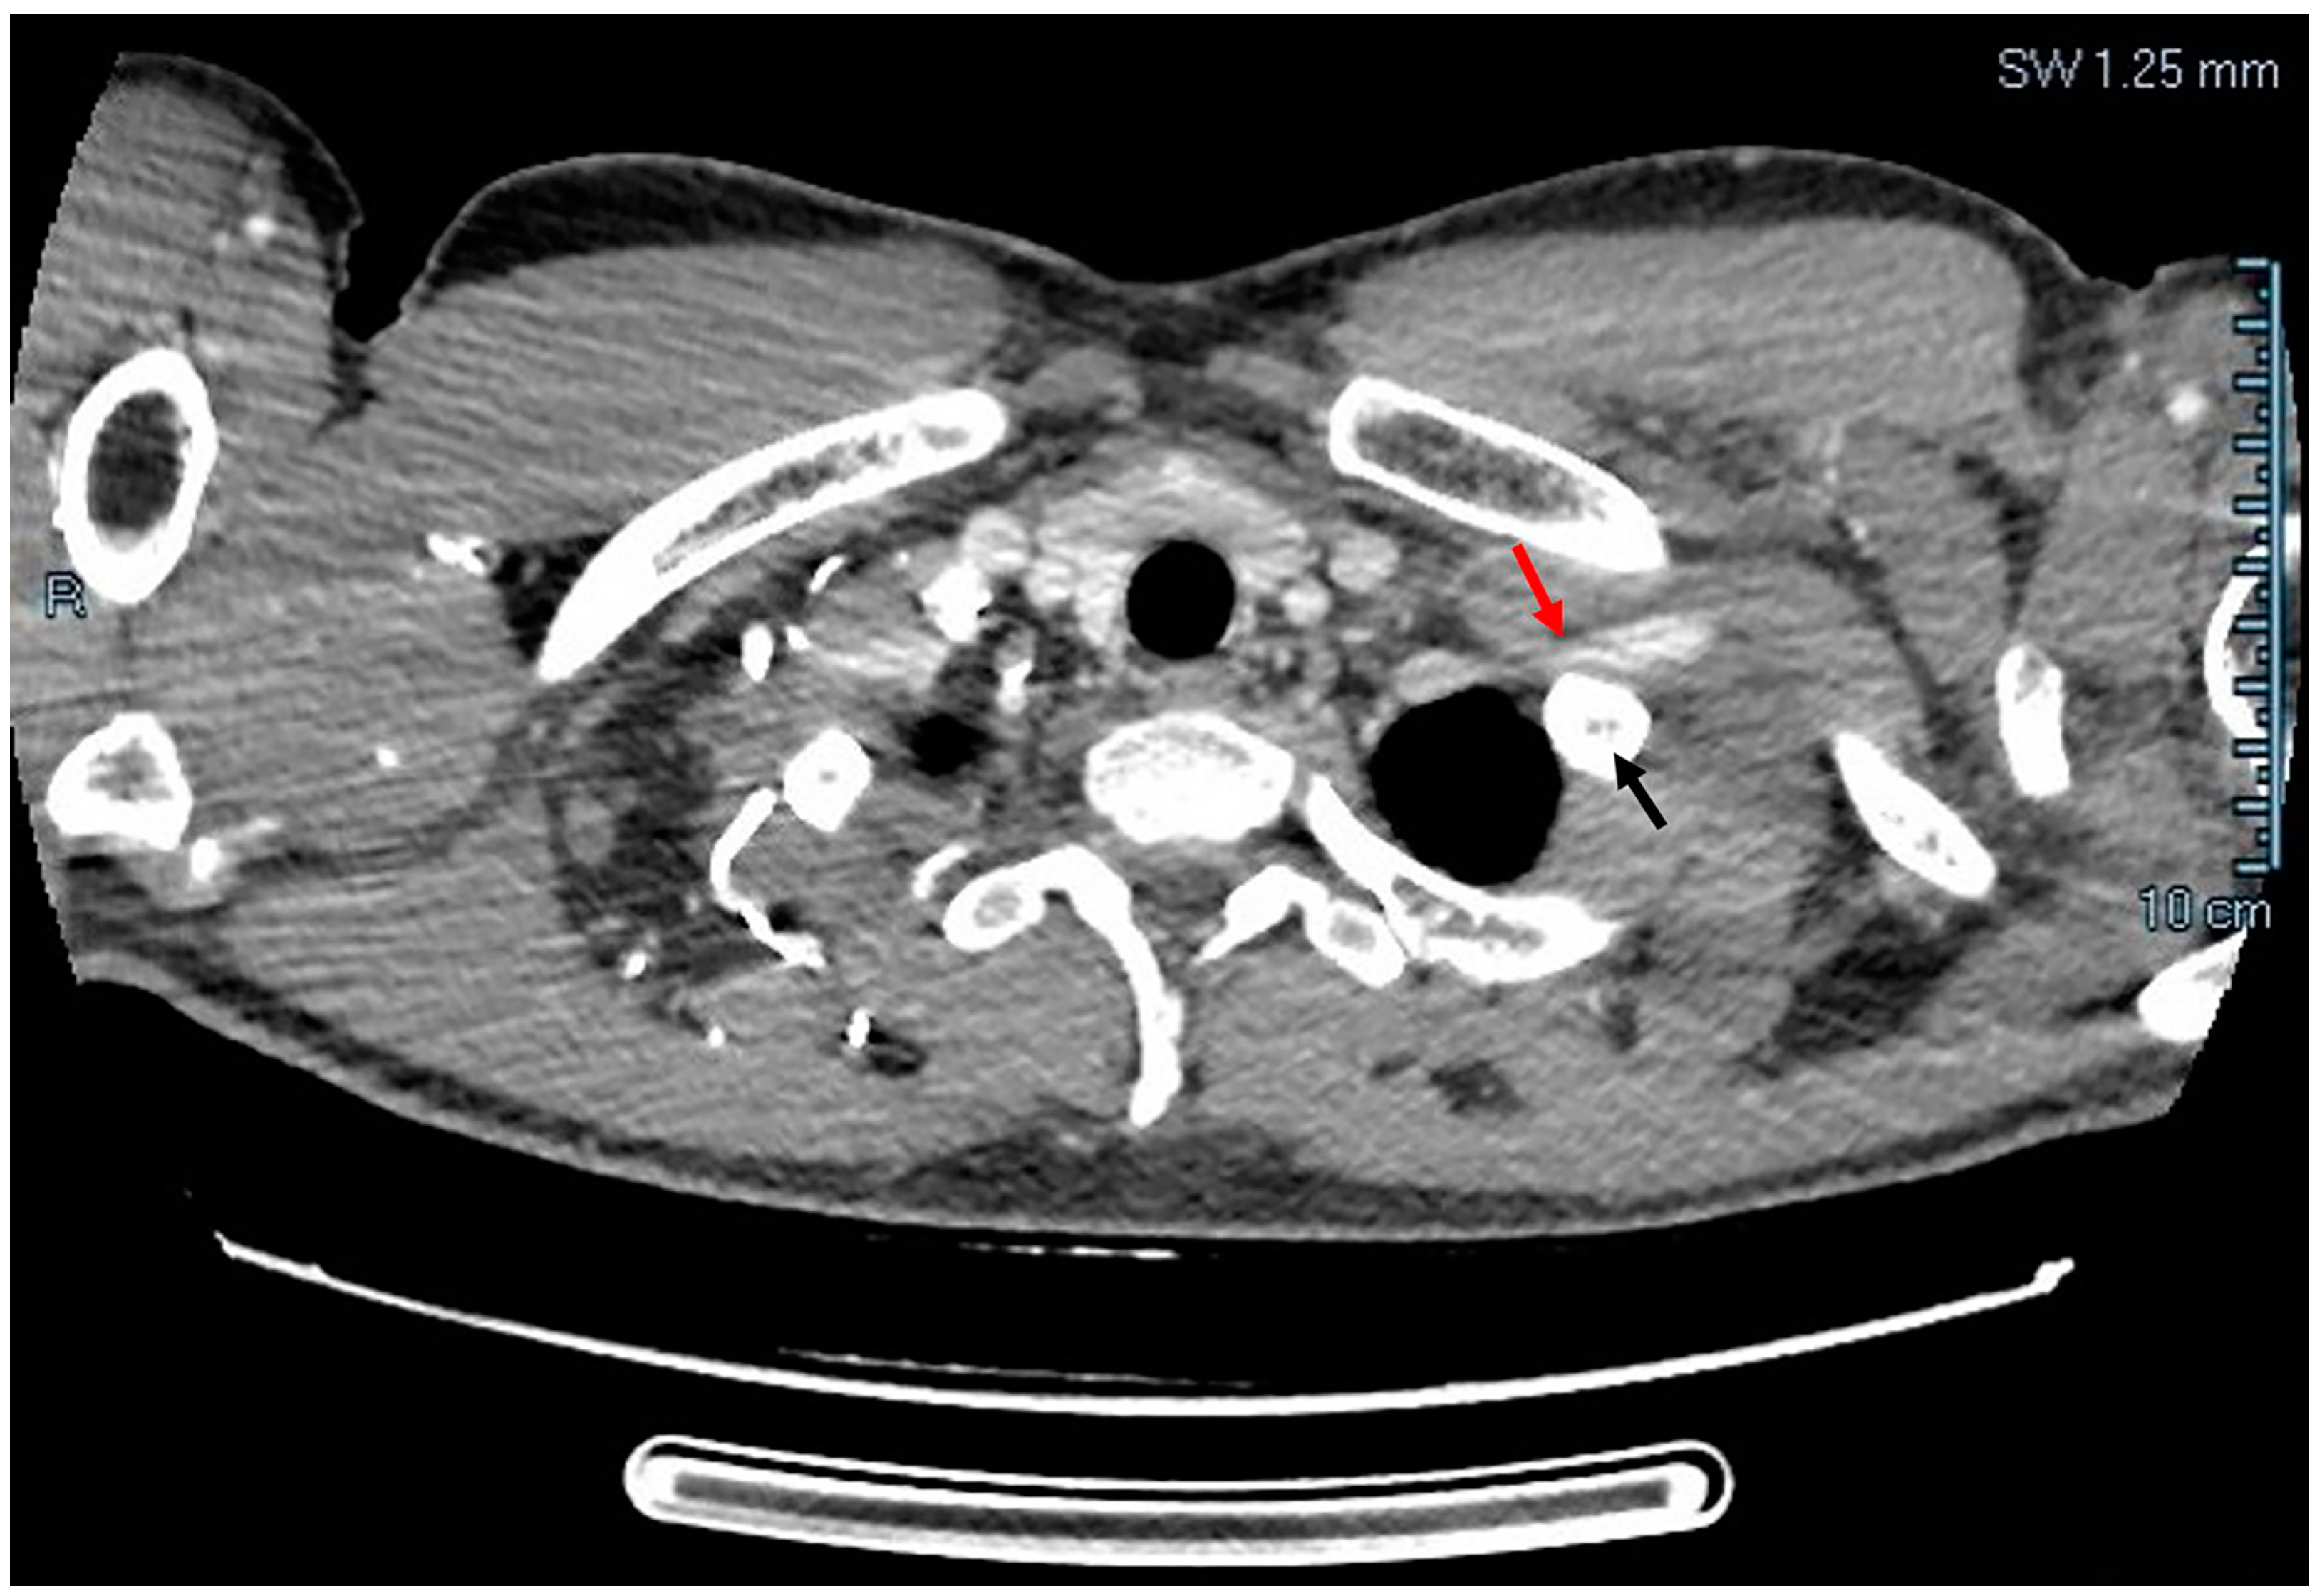

After establishing the diagnosis of thrombosis, the patient was further evaluated by the thoracic surgery team and CT angiography showed left subclavian vein compression at the level of first rib, as shown in Figure 2.

Figure 2. CT angiography: left subclavian vein compressed (red arrow) by first rib (black arrow).